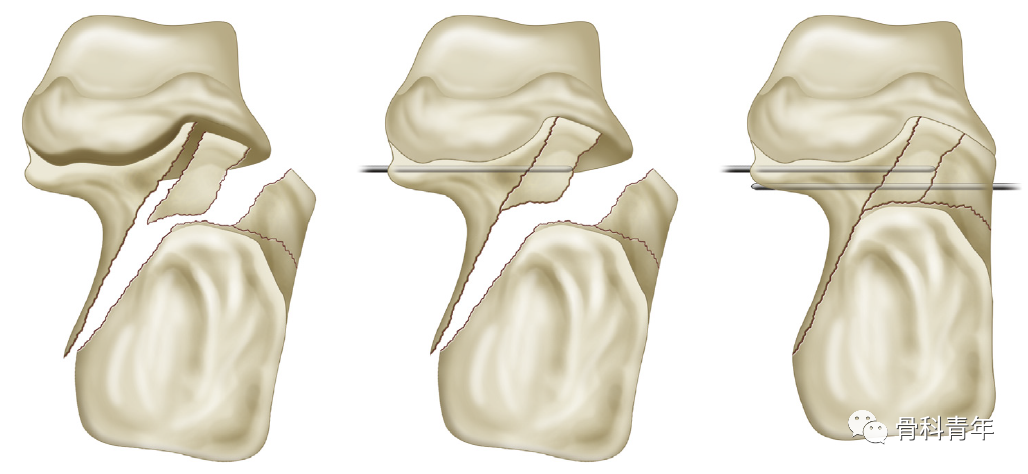

3. 骨折复位与固定皮瓣掀开后暴露跟骨外侧壁,此时跟骨外侧壁可能阻挡骨折复位及骨折线的观察,将外侧壁骨块取出;

将4.5mm斯氏针置入后外侧骨块,操作骨折块复位;将跟骨结节骨折块复位与载距突上,纠正内翻,恢复高度。并沿足底穿入克氏针临时固定。

将骨膜剥离子插入塌陷后关节面下方,撬拨复位。

克氏针临时固定复位的关节面,此时后关节面复位后如存在较大缺损,则需植骨;